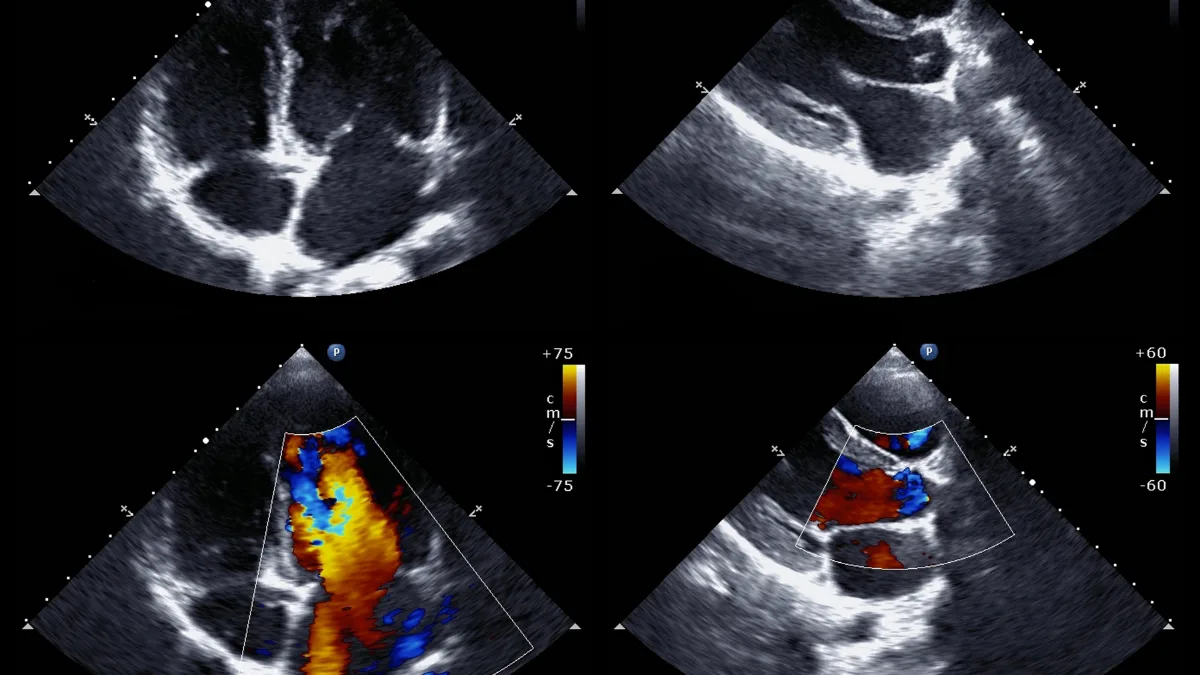

An echocardiogram uses the same ultrasound physics as a pregnancy scan, high-frequency sound waves emitted from a handheld probe, reflected back from internal structures, and converted into images on a monitor. There is no radiation involved at any point.

The cardiac sonographer positions the probe on the skin of the chest, applying a clear gel to eliminate the air gap between probe and skin, air blocks ultrasound transmission. By moving the probe to different positions around the chest, multiple viewing angles are obtained, providing a comprehensive assessment of every cardiac structure.

Doppler imaging, measuring blood flow

Modern echocardiography also uses Doppler imaging, which detects the speed and direction of blood flow through the heart. This allows the cardiologist to measure the severity of any valve narrowing or leaking with precision, tracking changes over time and informing decisions about whether and when surgical intervention is needed.

All four valves assessed for stenosis (narrowing) and regurgitation (leaking), with Doppler quantifying severity precisely.